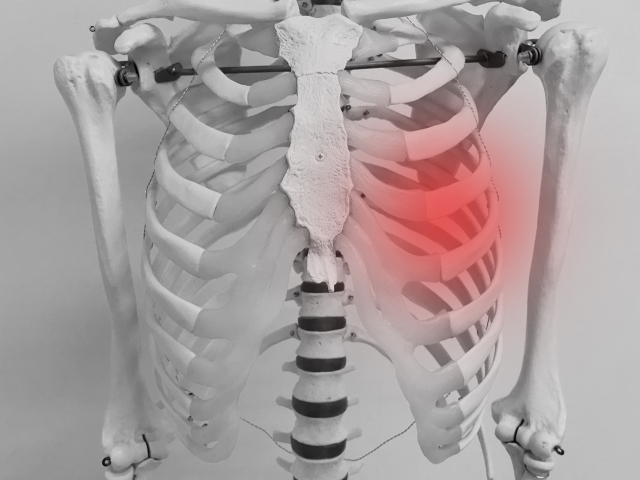

神経痛は、神経が圧迫されたり、損傷を受けたり、炎症を起こしたりすることによって引き起こされる痛みです。この痛みは通常、特定の神経の経路に沿って発生し、時にはその神経が支配する範囲に広がることが特徴です。神経痛の痛みは、しばしば鋭く、焼けるような感覚や電撃のような衝撃を伴います。

神経痛にはいくつかの一般的な形態があり、その中でも特によく知られているのが坐骨神経痛と三叉神経痛です。坐骨神経痛は、腰から足にかけての広範囲にわたる痛みを特徴とし、三叉神経痛は顔の特定の部分に激しい痛みを引き起こします。これらの症状は、それぞれ異なる神経が影響を受けることによって発生し、患者によって痛みの程度や性質が異なります。

外傷や過度の使用は、神経繊維に直接的な損傷を与えることがあり、これが神経痛の一般的な原因となります。事故による急激な衝撃や、スポーツ中の過度なストレッチ、長時間にわたる同じ姿勢の維持などが、神経を圧迫または引き伸ばし、炎症や損傷を引き起こすことがあります。これらの状況は、特に脊髄やその他の重要な神経経路に沿った神経に影響を及ぼし、慢性的な痛みを引き起こす可能性があります。

糖尿病は、高血糖が神経損傷を引き起こす主要な原因の一つです。この状態は、神経の血流を減少させ、神経繊維を徐々に損傷させることで神経痛を引き起こします。また、ヘルニアなどの疾患は、脊椎の構造的な問題が神経を圧迫し、痛みや不快感を引き起こすことがあります。これらの疾患による神経痛は、神経への持続的な影響により、慢性的な症状を引き起こすことが一般的です。